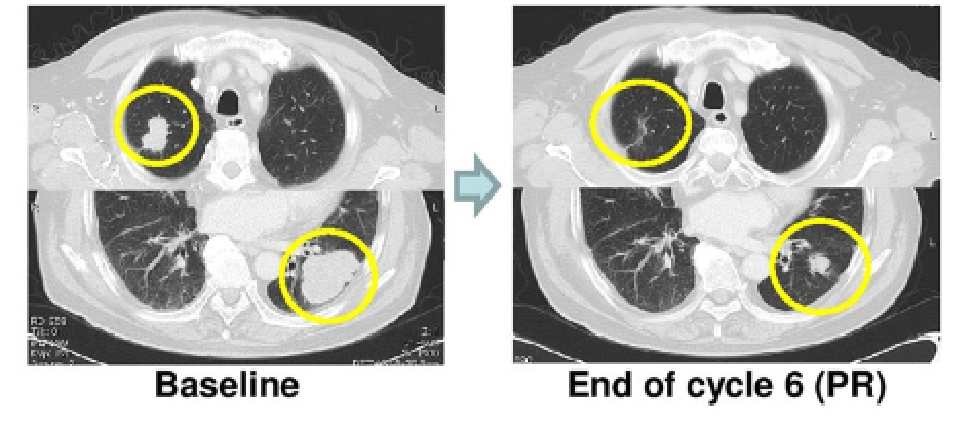

这项实验分为两个部分,第一部分的5名患者在接受Avastin (贝伐单抗)和氟尿嘧啶的维持治疗后再次接种了单剂量的PolyPEPI1018 疫苗治疗,然后进行12周的随访。第二部分,6名患者每12周接受三剂疫苗治疗。结果显示:在11名接种疫苗的患者中,3名病情进展,5名病情稳定,3名患者部分肿瘤缓解,其中两名的肿瘤已缩小到可以接受手术的范围,更值得一提的是,其中一位患者在手术后的原发肿瘤中发现已经没有存活的肿瘤细胞,这说明,癌症疫苗已经将肿瘤细胞全部杀灭。因此,PolyPEPI1018可有效恢复患者的免疫反应。用PolyPEPI1018疫苗进行的治疗和维持治疗是安全的,并初步证明了疫苗对MSS mCRC肿瘤具有早期临床活性的证据,能够有效的延缓肿瘤进展。这项结果另研究人员非常振奋。研究人员说,治疗是安全并且耐受良好,没有严重的不良事件,并且所有患者均产生了源自PolyPEPI1018的免疫反应。一次注射PolyPEPI1018会导致“前所未有的免疫学活性”,每位患者的T细胞靶向多达5种癌症蛋白,PolyPEPI1018与维持疗法配合使用时可以产生持久反应。PolyPEPI1018是一种现成的多肽疫苗,由六个合成蛋白片段组成,含有12种免疫原性表位,这些表位基于对2931次活检组织的分析而得自7种在mCRC中经常表达的保守癌抗原。疫苗可诱导针对大肠癌细胞中常见的七种癌抗原的免疫反应,从而产生针对大肠肿瘤的持久应答,同时对健康细胞没有损伤。目前这款疫苗的一期试验已经结束,我们期待这款能够延长结直肠癌患者生存期的疫苗能够尽快开展2,3期的临床试验。想了解详情的病友可以致电全球肿瘤医生网医学部。

有持续数据显示抗VEGF治疗可能与PD-1阻断有协同作用。现在,这是MSS人群中的第一次,通过结合这两种治疗策略,看到了非常令人印象深刻的疗效。因此,通过将抗VEGF策略与免疫检查点抑制结合起来,MSS疾病患者将会有更大的生存获益。77岁男性,RAS野生型转移性直肠癌,MSS, PD-L1 CPS=0。FOLFIRI+Bevacizumab, FOLFOX, irinotecan+cetuximab,trifluridine/tipiracil后进展一项研究分析了20例患者,有2例患者出现PR,疗效都持续了44周及44周以上,另外2例患者出现疾病稳定,DCR为20%。16例患者出现≥3级AE,1例患者出现死亡。对于后线难治性MSS型结直肠癌患者,治疗方案非常有限,该免疫联合方案展现了一定的疗效。进入靶向免疫治疗新时代,每个患有结直肠癌的患者都应该通过MSI检测、RAS和BRAF的突变分析,并且尽可能进行HER2扩增,NTRK等基因的检测,基因检测(NGS)将纳入大多数患者的初步检查标准。现在国内的患者可通过全球肿瘤医生网进行检测4006667998。